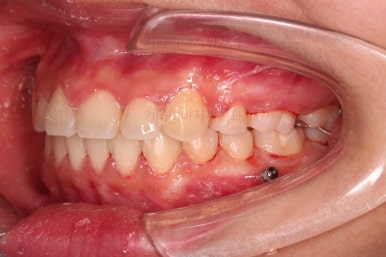

점점 틈새가 붙어가는게 보이죠?

계속 반복합니다.

틈새는 거의 다 붙어가는데 교합이나 중앙선 등을 위해 추가적으로 밀고 당기기를 해줍니다.

디테일을 좀 더 맞추고 부산치아교정 마무리를 합니다.

치아 갯수 및 사이즈 문제로 위아래의 정중선은 100% 일치시키긴 힘들지만 가능한 선에서 최대한 맞추었고요.

윗니가 1개 없는 상태에서의 교합도 잘 맞추고 마무리를 했습니다.